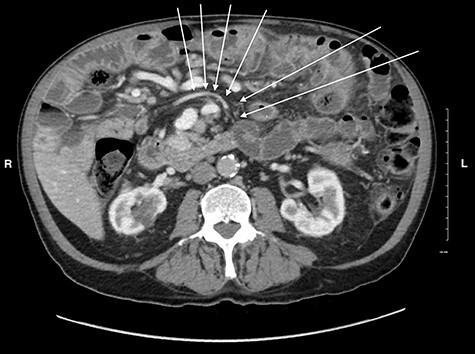

Midgut volvulus is an uncommon disease most often presenting in children, with rare occurrences in adults [3]. It is characterized by an abnormal rotation of the intestine around a fixed-point. Associated congenital conditions include gastrointestinal malrotation, jejunoileal diverticulosis and a history of abdominal wall defects [5, 6]. Acutely, volvulus can be intermittent or complete, with variable symptoms, leading to obstruction, bowel necrosis and possibly death. Chronic presentations of midgut volvulus can also occur, resulting in recurrent pain, intermittent obstruction and malabsorption over months to years. Due to its rarity in adults and variable presentation, preoperative diagnosis of intestinal volvulus is challenging. Adding to this difficulty, a classic ‘whirlpool sign’ or abnormal superior mesenteric vessel configuration is only present on CT in 30.9 and 58% of cases, respectively [3]. Retrospectively, the right-sided position of the duodenojejunal flexure and slight swirling of small bowel mesentery is visible but clouded by numerous jejunoileal diverticula (Figs 5 and 6).

CT image showing a subtle swirl of the mesenteric vein, coursing from the left to the right side of the abdomen indicating volvulus of the small bowel.